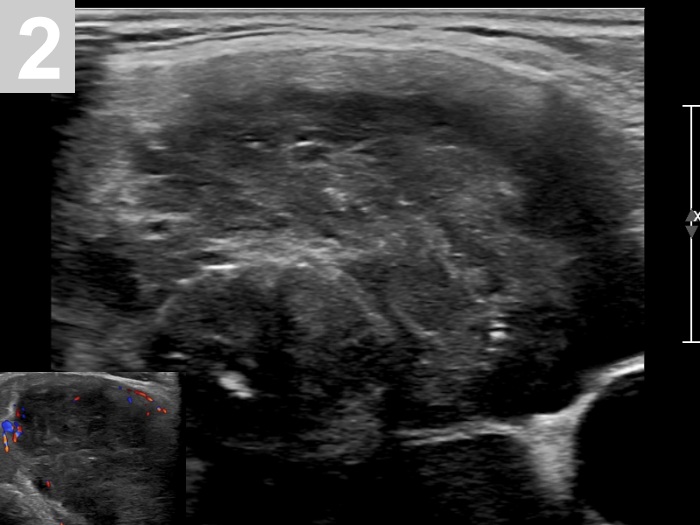

3 US of thyroid cancer

Pre- and postoperative ultrasound in thyroid cancers

Cases to be discussed on January 18, 2024